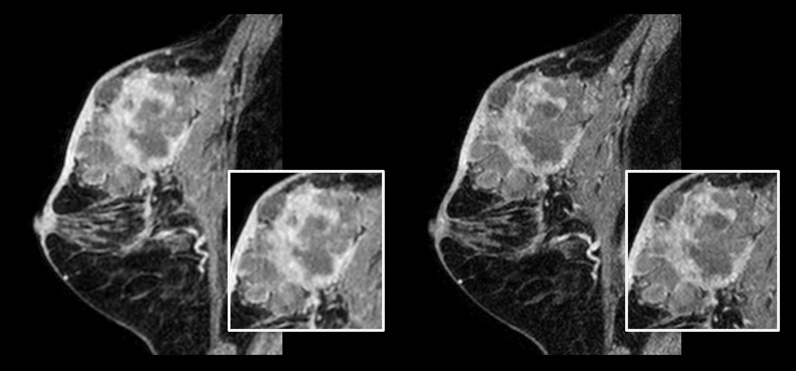

Patient with breast cancer.

On the left: Conventional 3D mDIXON XD scan with 1.0 mm isotropic voxel size in a scan time of 2:22 min

On the right: Compressed SENSE 3D mDIXON XD scan with 0.8 mm isotropic voxel size in a scan time of 2:21 min.

Courtesy: Kurashiki Central Hospital, Okayama. Japan

In breast scanning, high resolution is important to help me identify very small mammary lesions, so, we need high spatial resolution in 2D T1- and T2-weighted images, as well as a short scan time. Compressed SENSE has allowed us to increase spatial resolution, which benefits our diagnostic confidence.”

Dr. Takashi Koyama, MD, PhD, Diagnostic Radiologist and Director of the Department of Radiology Center and Diagnostic Radiology, Kurashiki Central Hospital, Japan